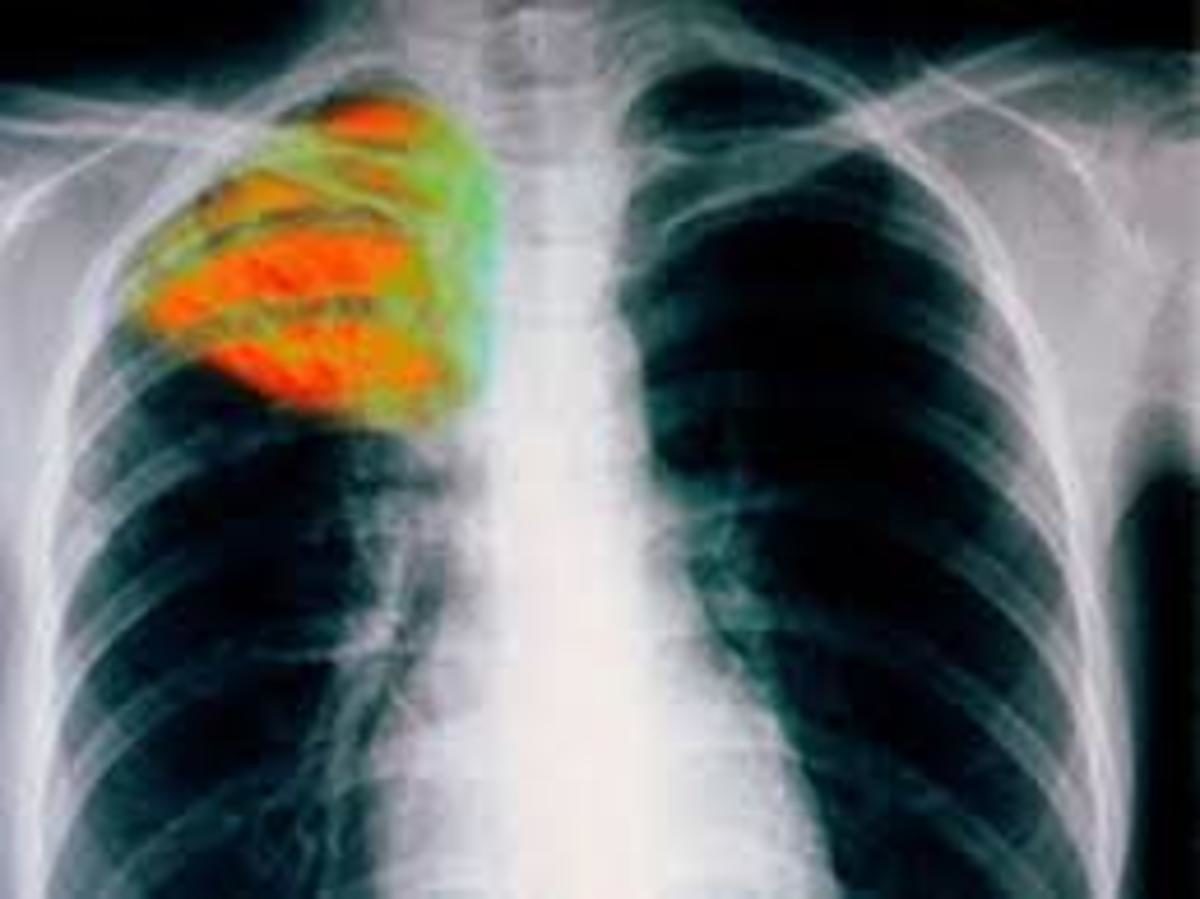

Παγκόσμια ημέρα: Η φυματίωση παραμένει προτεραιότητα του ΚΕΕΛΠΝΟ!

Η σημερινή ημέρα έχει καθιερωθεί από τον Παγκόσμιο Οργανισμό Υγείας ως Παγκόσμια Ημέρα Φυματίωσης. Σύμφωνα με στοιχεία του ΚΕΕΛΠΝΟ τα τελευταία δημοσιευμένα στοιχεία του Παγκόσμιου Οργανισμού Υγείας (WHO) και του Ευρωπαϊκού Κέντρου Πρόληψης και Ελέγχου Νοσημάτων (ECDC), το 2013 καταγράφηκαν παγκοσμίως 9.000.000 κρούσματα φυματίωσης, από τα οποία 360.000 στην Ευρώπη (Ευρωπαϊκό γραφείο Παγκόσμιου Οργανισμού Υγείας (ΠΟΥ)) .

Βάση των ίδιων στοιχείων επίσης, 1.500.000 άνθρωποι παγκοσμίως πέθαναν από φυματίωση, με το υψηλότερο ποσοστό θανάτων να έχει καταγραφεί στις φτωχές χώρες, καθώς επίσης και μεταξύ ατόμων με HIV λοίμωξη.